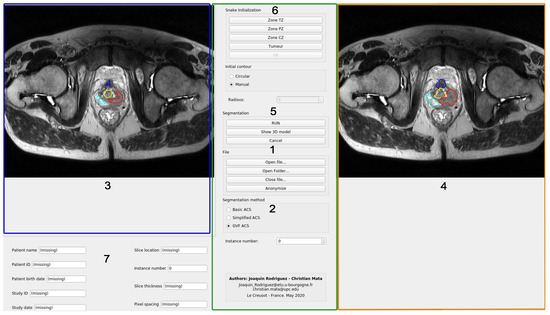

In this section, the code organization and the user interface of the program will be explained. The main window of the program is shown in Figure 3. All the code has been developed in Python, using the modules PyQt for the user interface and PyDicom to open the files included in the testing dataset. The code has been organized in modules that do not interact with each other. The integration of all of them has been made in the Main Window class.

The data available to the user includes the images and the patient data fields. This module is also in charge of anonymizing the files and writing them into disc. The functionalities of this module can be accessed through the buttons in the Section 1 of the Figure 3.

• Image segmentation. This module stores all the Python code related to the segmentation procedure. The main class in this module is Segmentation-Hub, which is in charge of selecting the right class for the object that will produce the segmentation, according to the method chosen by the user. The selection of the segmentation method can be done in Section 2 of Figure 3. By implementing the methods in this manner, the actual implementation of the segmentation task is completely transparent for other classes that make use of this module. To select certain segmentation method, only a label that defines the method must be provided.

• Image widget. This module is in charge of showing the image, as well as the initial and the resulting contours from the segmentation. The same module is used for both, left and right images. It also captures the clicks from the user to generate either the circular or the manual initial contour. Both types of initialization will be explained later. The image widget is represented in Sections 3 and 4 of Figure 3.

• Model 3D widget. It shows a 3D representation of the output segmentation, based on the Python module Matplotlib. This process is relatively simple as it only replicates the given contour vertically. If the spatial resolution is given in the input DICOM file, the scale of the axis will be given in millimeters. It can be accessed through the button S h o w 3 D M o d e l located in Section 5 of Figure 3.

• Snake init widget. This widget is in charge of handling all the functionalities of the Snake initialization group, placed at the top of the central control panel of the application.

Afterwards, the corresponding masks for those contours can be generated for the snake algorithm (the mask consists of an image with values of 1 in the interior of the contour, and zeros outside of it). The interface for this module is represented in Section 6 of Figure 3.

• User data widget. It is implemented as an efficient and easy to use manner to handle all the user information as an object, and to show it. This class stores all the information related to the patient or the study, retrieved from the DICOM file. It also contains the corresponding widgets that are shown below the left image area, where the gathered information is displayed (see Section 7 of Figure 3).

Finally, regarding the user interface showed in Figure 3, this program has four well-defined sections:

• Left panel. In this area (highlighted in blue), the loaded images are shown, and the user can draw the initial contours of the snake of the different areas of the prostate. Each prostate zone is surrounded with a different color to make it easily distinguishable (see Figure 3)

• Right panel. This area (highlighted in orange) shows the loaded images, and the results of the evolution of the selected snake algorithm. Each prostate zone has a pre-defined color, and they match with the colors used for the initial contours (see Section 4 of Figure 3).

• Bottom area. The patient information retrieved from the DICOM file is shown (highlighted in blue). Moreover, information related to the spatial resolution and thickness of the gathered slice are included (Section 7 of Figure 3)

• Central area. This is the control panel area (highlighted in green). All the functionalities and possible configurations of the program are located in this area. It is represented in the Sections 1, 2, 5 and 6 of Figure 3.

Figure 3. GUI interface of the developed active contour segmentation tool using a prostate MR image.

Applsci 10 06163 g003